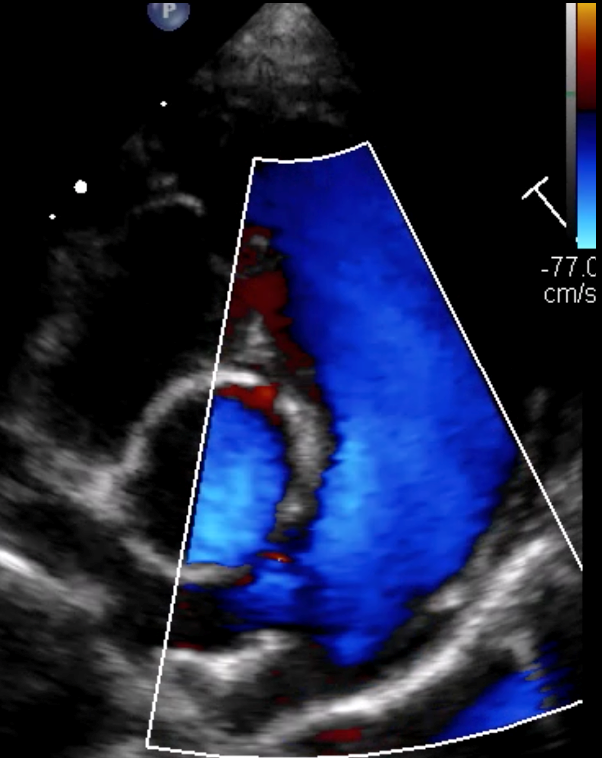

• Utiliser les anomalies observées en modes 2D, TM et Doppler pour classifier et graduer les cardiopathies acquises.

• Étude de cas interactifs à partir d’images fixes et de vidéos en échographie cardiaque (modes 2D, TM, Doppler).

• Principes de l’échocardiographie 2D, TM et Doppler appliqués aux cardiopathies acquises.